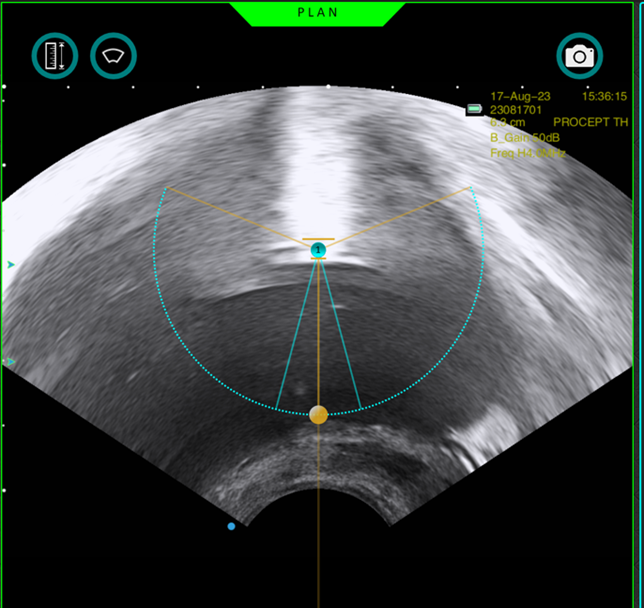

아쿠아 블레이션 수술 과정

초음파와 내시경을 동시에 실시간으로 확인하며 절제할 조직과 보존할 조직을 정확히 설계

수술 전 막혀있는 전립선 초음파 소견

수술 후 잘 열린 전립선 초음파 소견